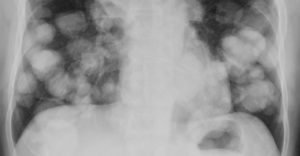

К 4 степени рак дал метастазы в соседние органы и ткани: поразил брюшную полость, сосуды, надпочечники. Нередко обнаруживаются и отдаленные патологические очаги — в печени, легких, костях. Сама почка или обе подверглись генерализованному некрозу с полным прекращением работы. Такие масштабные нарушения в организме ведут к выраженной клинической картине.

- кровохарканье и лающий кашель при проникновении в легкие;

Применяется химиотерапия (таргетная) для уничтожения метастаз и уменьшения первичной опухоли. По результатам принимается решение об операции. Как правило, проводится радикальная нефрэктомия с удалением метастаз.

Лечение рака почки 4 стадии облучением актуально лишь при распространении рака к кости.